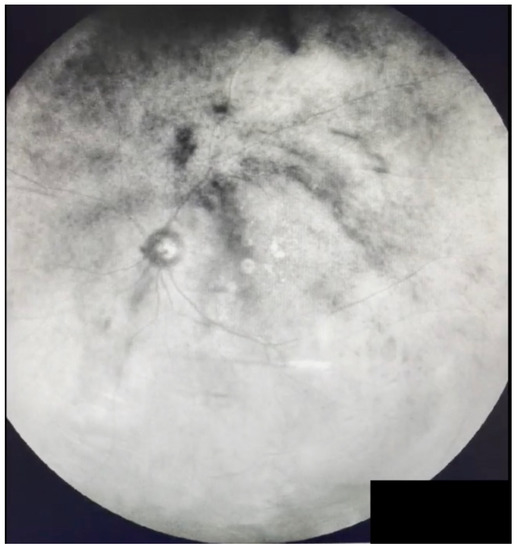

Figure 5.

Ultra-widefield IRcSLO image of an eye with Grade 3 vitreous floaters. This still image was obtained after an upward saccade and shows a dense shadow inside the macular area (arrow). See also Video S5.